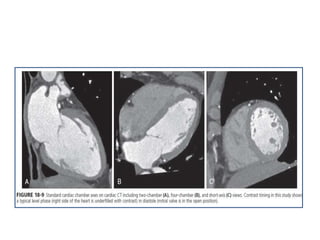

VENTRICULAR AND VALVULAR MORPHOLOGY AND

FUNCTION

• Helical scan acquisitions, allow

reconstruction of cardiac CT data

from both systolic and diastolic